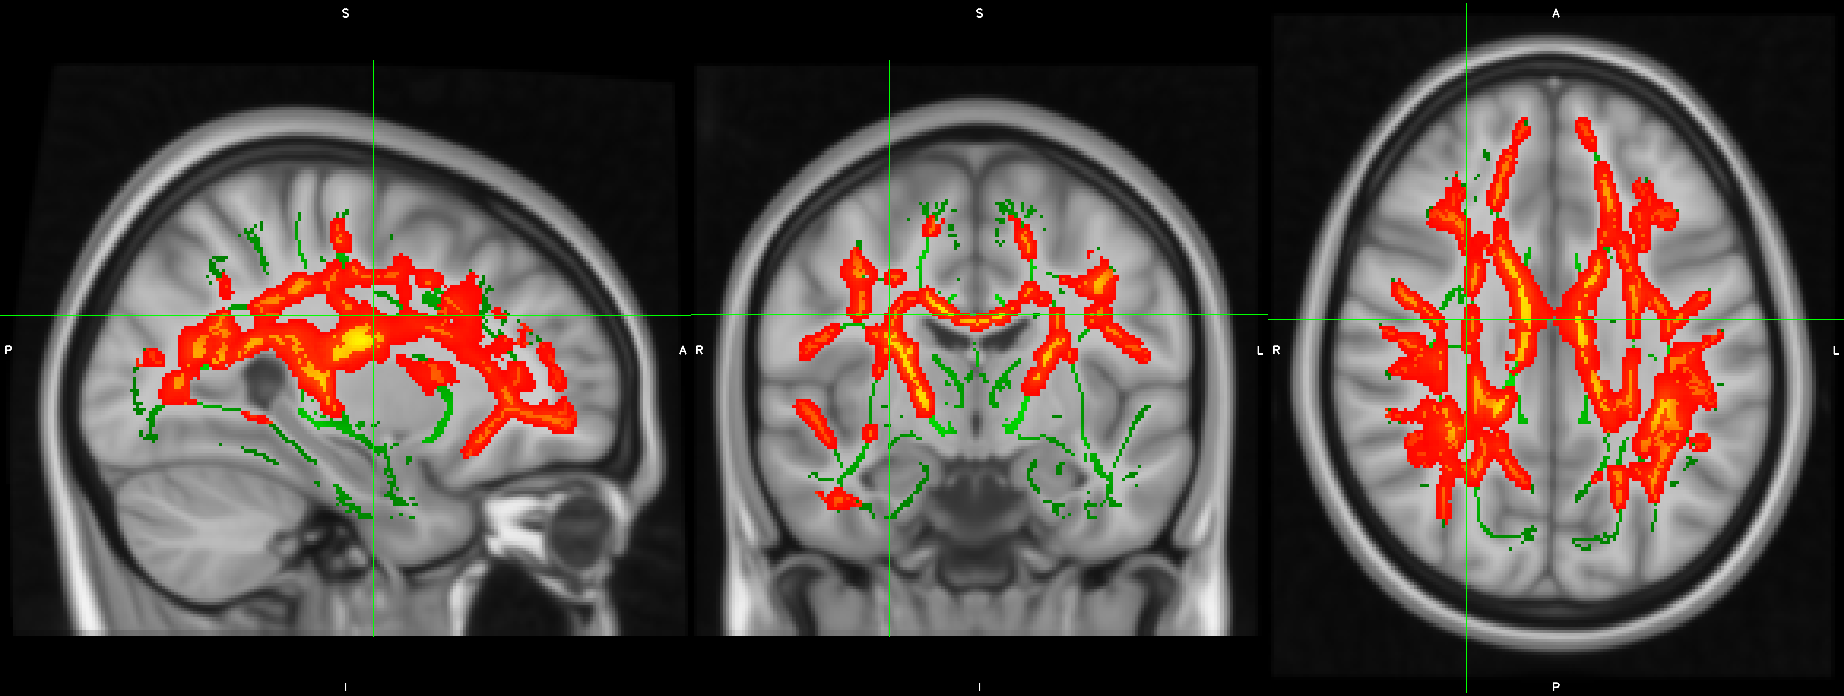

Imatges de ressonància magnètica cerebral que mostren les àrees de la matèria blanca on els canvis en inflamació cerebral associats al tractament antipsicòtic varien segons el consum previ de cànnabis.

A l'estudi hi han participat 62 pacients diagnosticats de forma recent i 38 controls. I els resultats del treball mostren diferències en la inflamació cerebral entre les persones que pateixen un primer episodi psicòtic en funció de si consumeixen cànnabis o no. Diferències que també es veuen en les persones que no tenen psicosi, encara que consumeixin. Un fet que, segons el Dr. Daniel Bergé, psiquiatre de l'Hospital del Mar i membre del Grup de Recerca en Neuroimatge en Trastorns Mentals de l'Hospital del Mar Research Institute, "suggereix una associació entre l'ús de cànnabis i alteracions en el sistema inflamatori en els primers episodis psicòtics". A la vegada, els resultats obtinguts indiquen que el cànnabis pot influir en la capacitat dels tractaments contra la psicosi de reduir aquesta inflamació. En aquest sentit, "la potencial associació del consum d'aquesta substància amb l'alteració de la reducció de la inflamació cerebral assolida gràcies als tractaments antipsicòtics ens ofereix una visió d'un dels possibles factors que influeixen en el baix èxit del tractament en aquests pacients", afegeix el Dr. Bergé.